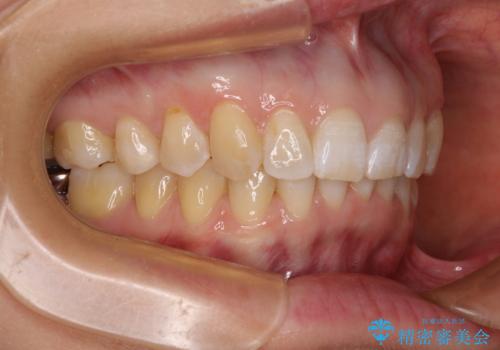

- 上顎前歯の前方に傾斜した咬み合わせを気にして来院された患者様です。

奥歯の咬み合わせを見ると、上顎が下顎に対して相対的に前方にありました。

深い咬み合わせを改善するためには、上顎臼歯を後方に移動させつつ、下顎の小臼歯を直立させる必要があります。

インビザライン単体で対応ることも検討できますが、達成する可能性が低いため、カリエールディスタライザーという補助装置を併用して、より確実性を上げることとしました。

奥歯の咬み合わせと深い咬み合わせを改善した後、インビザラインで歯列を整えることとしました。